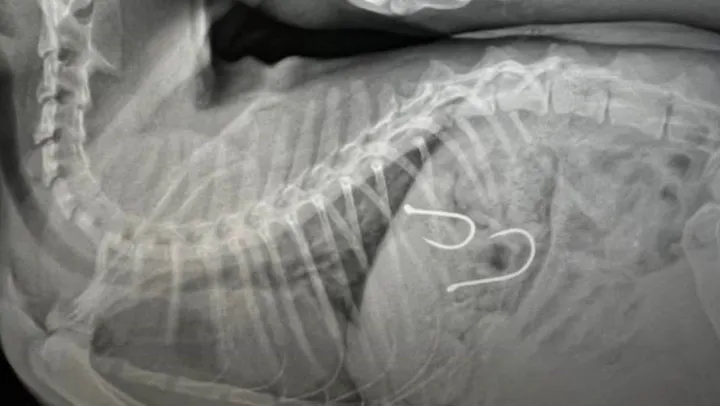

Sahil bandında dolaşan vatandaşlar, bir kedinin ağzından olta misinası sarktığını fark edince durumu Balıkesir Büyükşehir Belediyesi Sokak Hayvanları Tedavi Merkezi'ne ihbar etmişlerdi. Gelen ihbar üzerine kedi, ekipler tarafından müşahede altına alınmış ve sağlık durumu kritik olan yaralı hayvana acil olarak müdahale edilmişti. Çekilen röntgen sonucunda olta iğnelerinin kedinin midesine saplandığı anlaşılmış ve sonrasında ise kedi ameliyata alınmıştı.

Kedinin sağlık durumu ile ilgili Balıkesir Büyükşehir Belediyesi Sokak Hayvanları Tedavi Merkezi'nden edinilen son bilgilere göre, 2 adet olta iğnesi ve misinasının kedinin midesinden başarılı bir operasyonla çıkarıldığı, olta kancasının enfeksiyon oluşturma riskine karşı, antibiyotik ve serum tedavisine başlandığı belirtildi. Kedinin genel sağlık durumunda şu an için bir olumsuzluğun söz konusu olmadığı ve 48 saat yoğun bakımda tutulacağı aktarıldı.